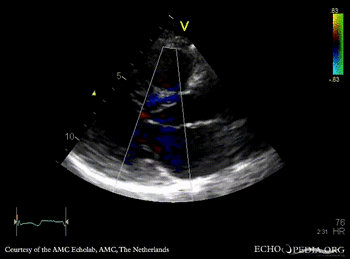

A3CH with Color Doppler: high velocity turbulent flow in LVOT A4CH with Color Doppler: high velocity turbulent flow in LVOT and in the middle of left ventricle